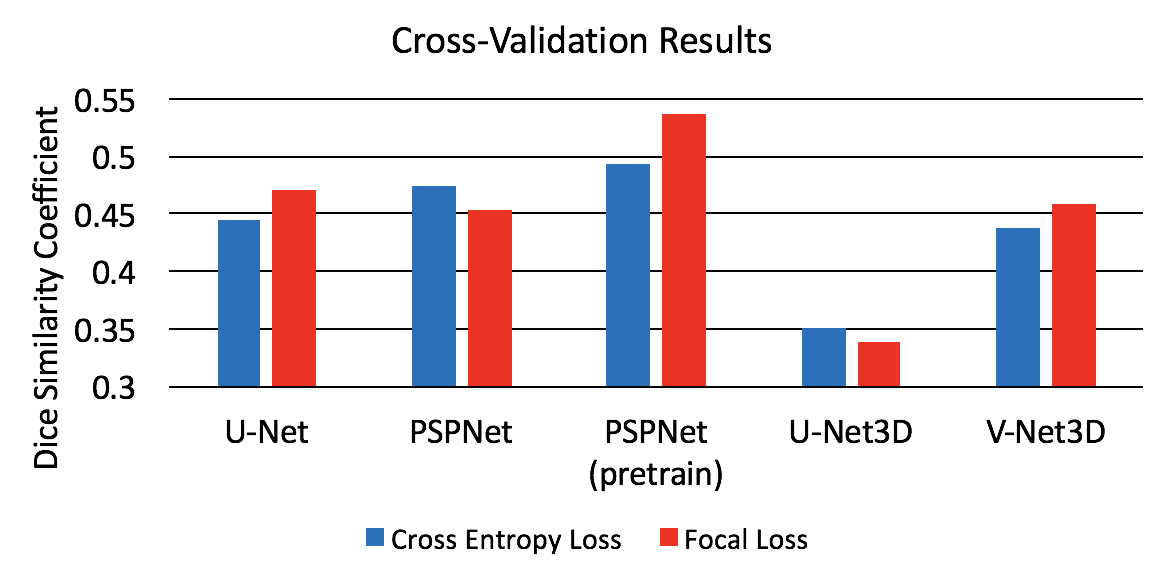

5.1 5-fold Cross Validation Results

The model parameters for each network were selected based on the best validation dice score. We performed a 5-fold cross-validation to determine model performance. The results are shown on Fig. 3. The pre-trained PSPNet with focal loss demonstrated the strongest 5-fold cross-validation results (). The 2D U-Net and PSPNet trained from scratch had a similar performance, so the pretraining using our additional input layer improved performance by approximately dice points. Additionally, the focal loss improved the pre-trained network substantially. Table 1 shows the per fold DSC results for the pre-trained PSPNet, trained using focal loss and cross entropy. From the table, it can be seen that some validation folds are more challenging than others, leading to varied DSC scores. Overall, usage of focal loss led to an improved overall DSC () compared to cross entropy (). We hypothesize this is due to the fact that the pretraining helps classify the obvious stroke lesion examples, but the focal loss forces the network to learn the more difficult samples.

The 3D networks performed poorly. We observed that their increased number of parameters resulted in more overfitting. Additionally, they were unable to take full advantage of the third image dimension, due to the large number of scans with only 2 axial slices. For the two best models, the 2D U-Net and pre-trained PSPNet, we observe the focal loss improved model performance. We demonstrate in Fig. 4 that the focal loss predicted more fine details in the lesions that were missed by cross entropy in the pre-trained PSPNet. The cross entropy loss network often over-predicted larger lesions than the focal loss network, and the focal loss network was able to more closely predict the fine appearance features of the lesions, and predict areas that cross entropy completely missed.